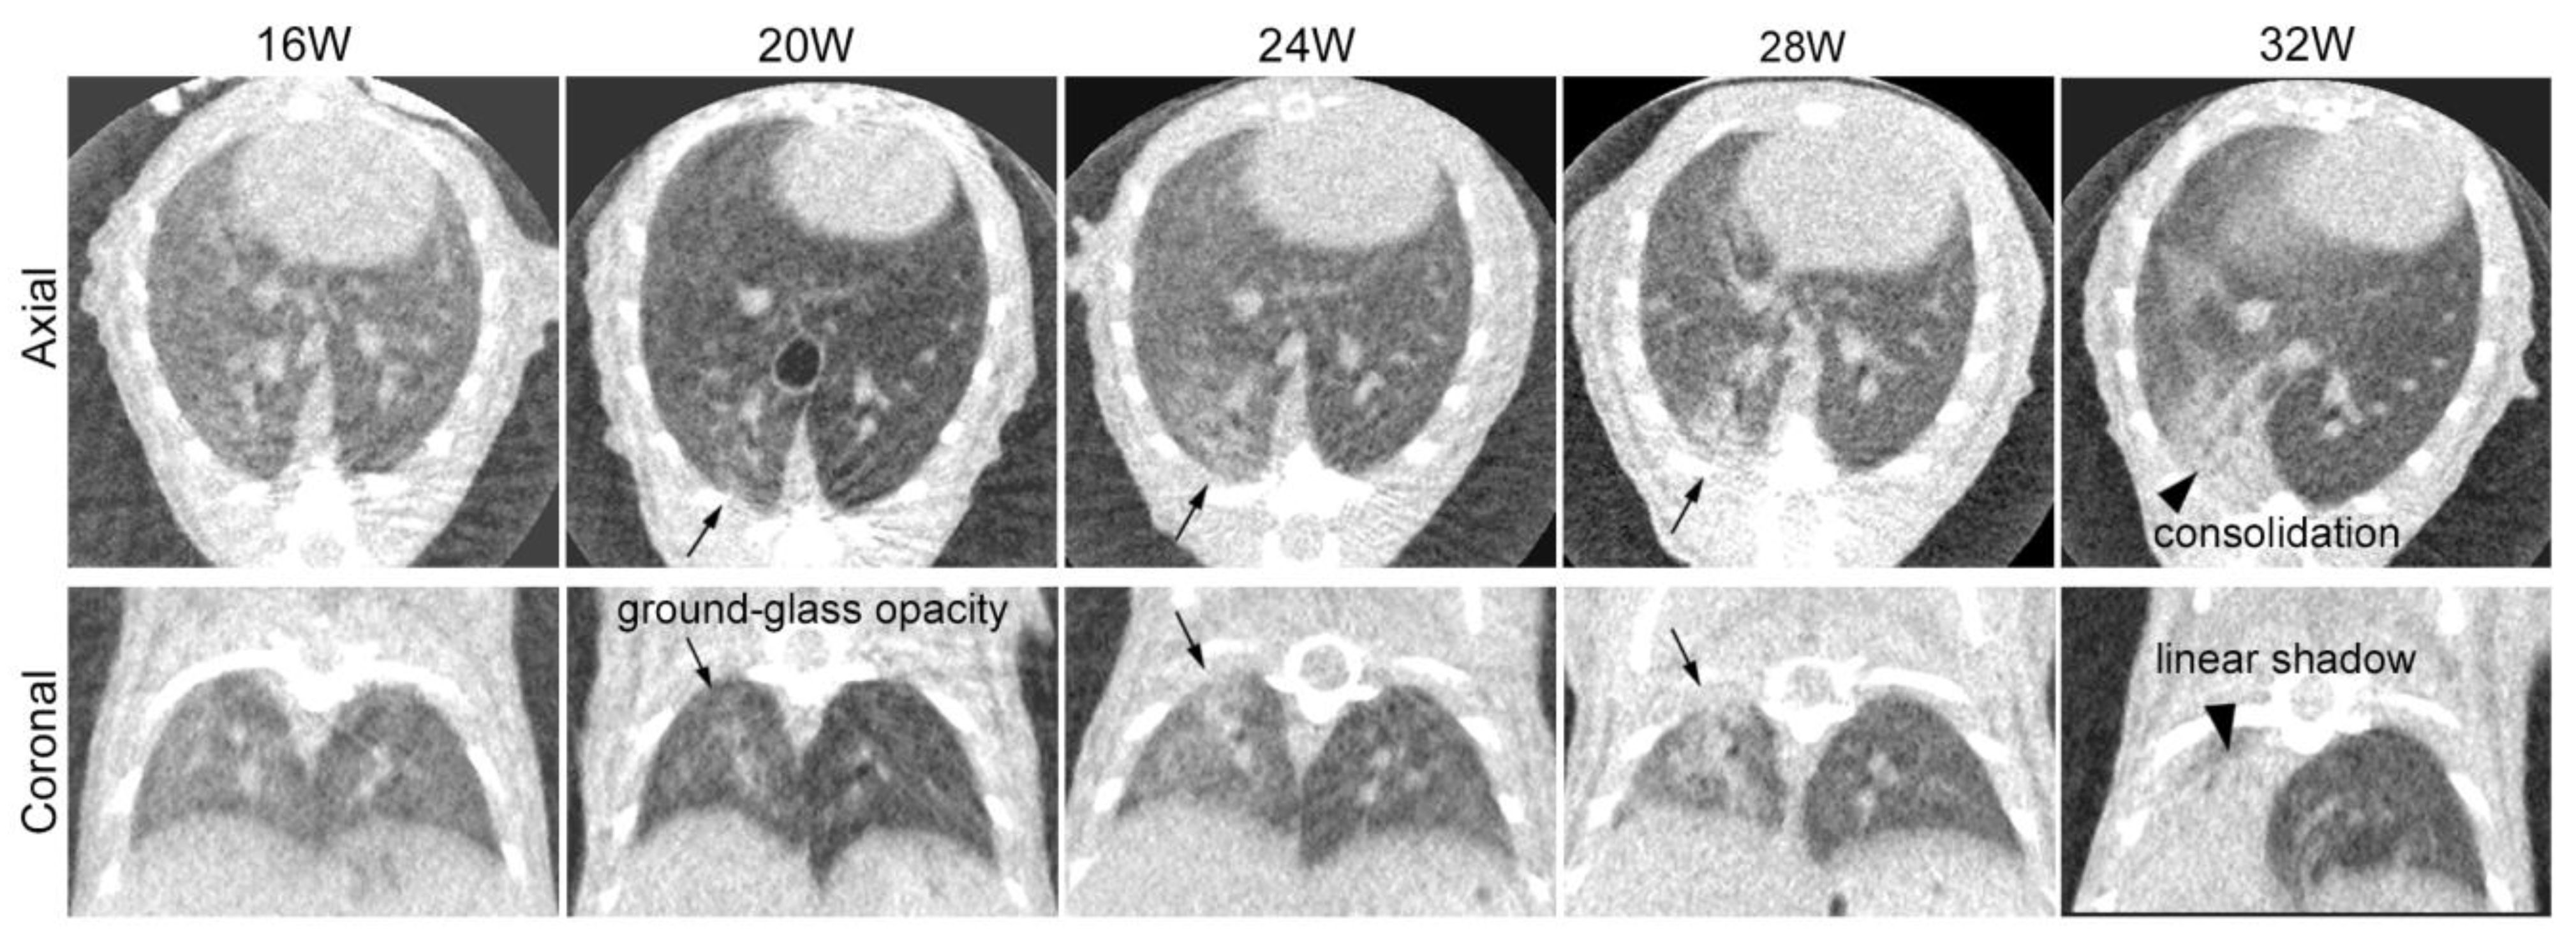

3.1. Sequential CT Image Changes in Focally Irradiated Lung of Mouse with 30 Gy/1fr

4.2. Sequential Changes in CT Images after Irradiation